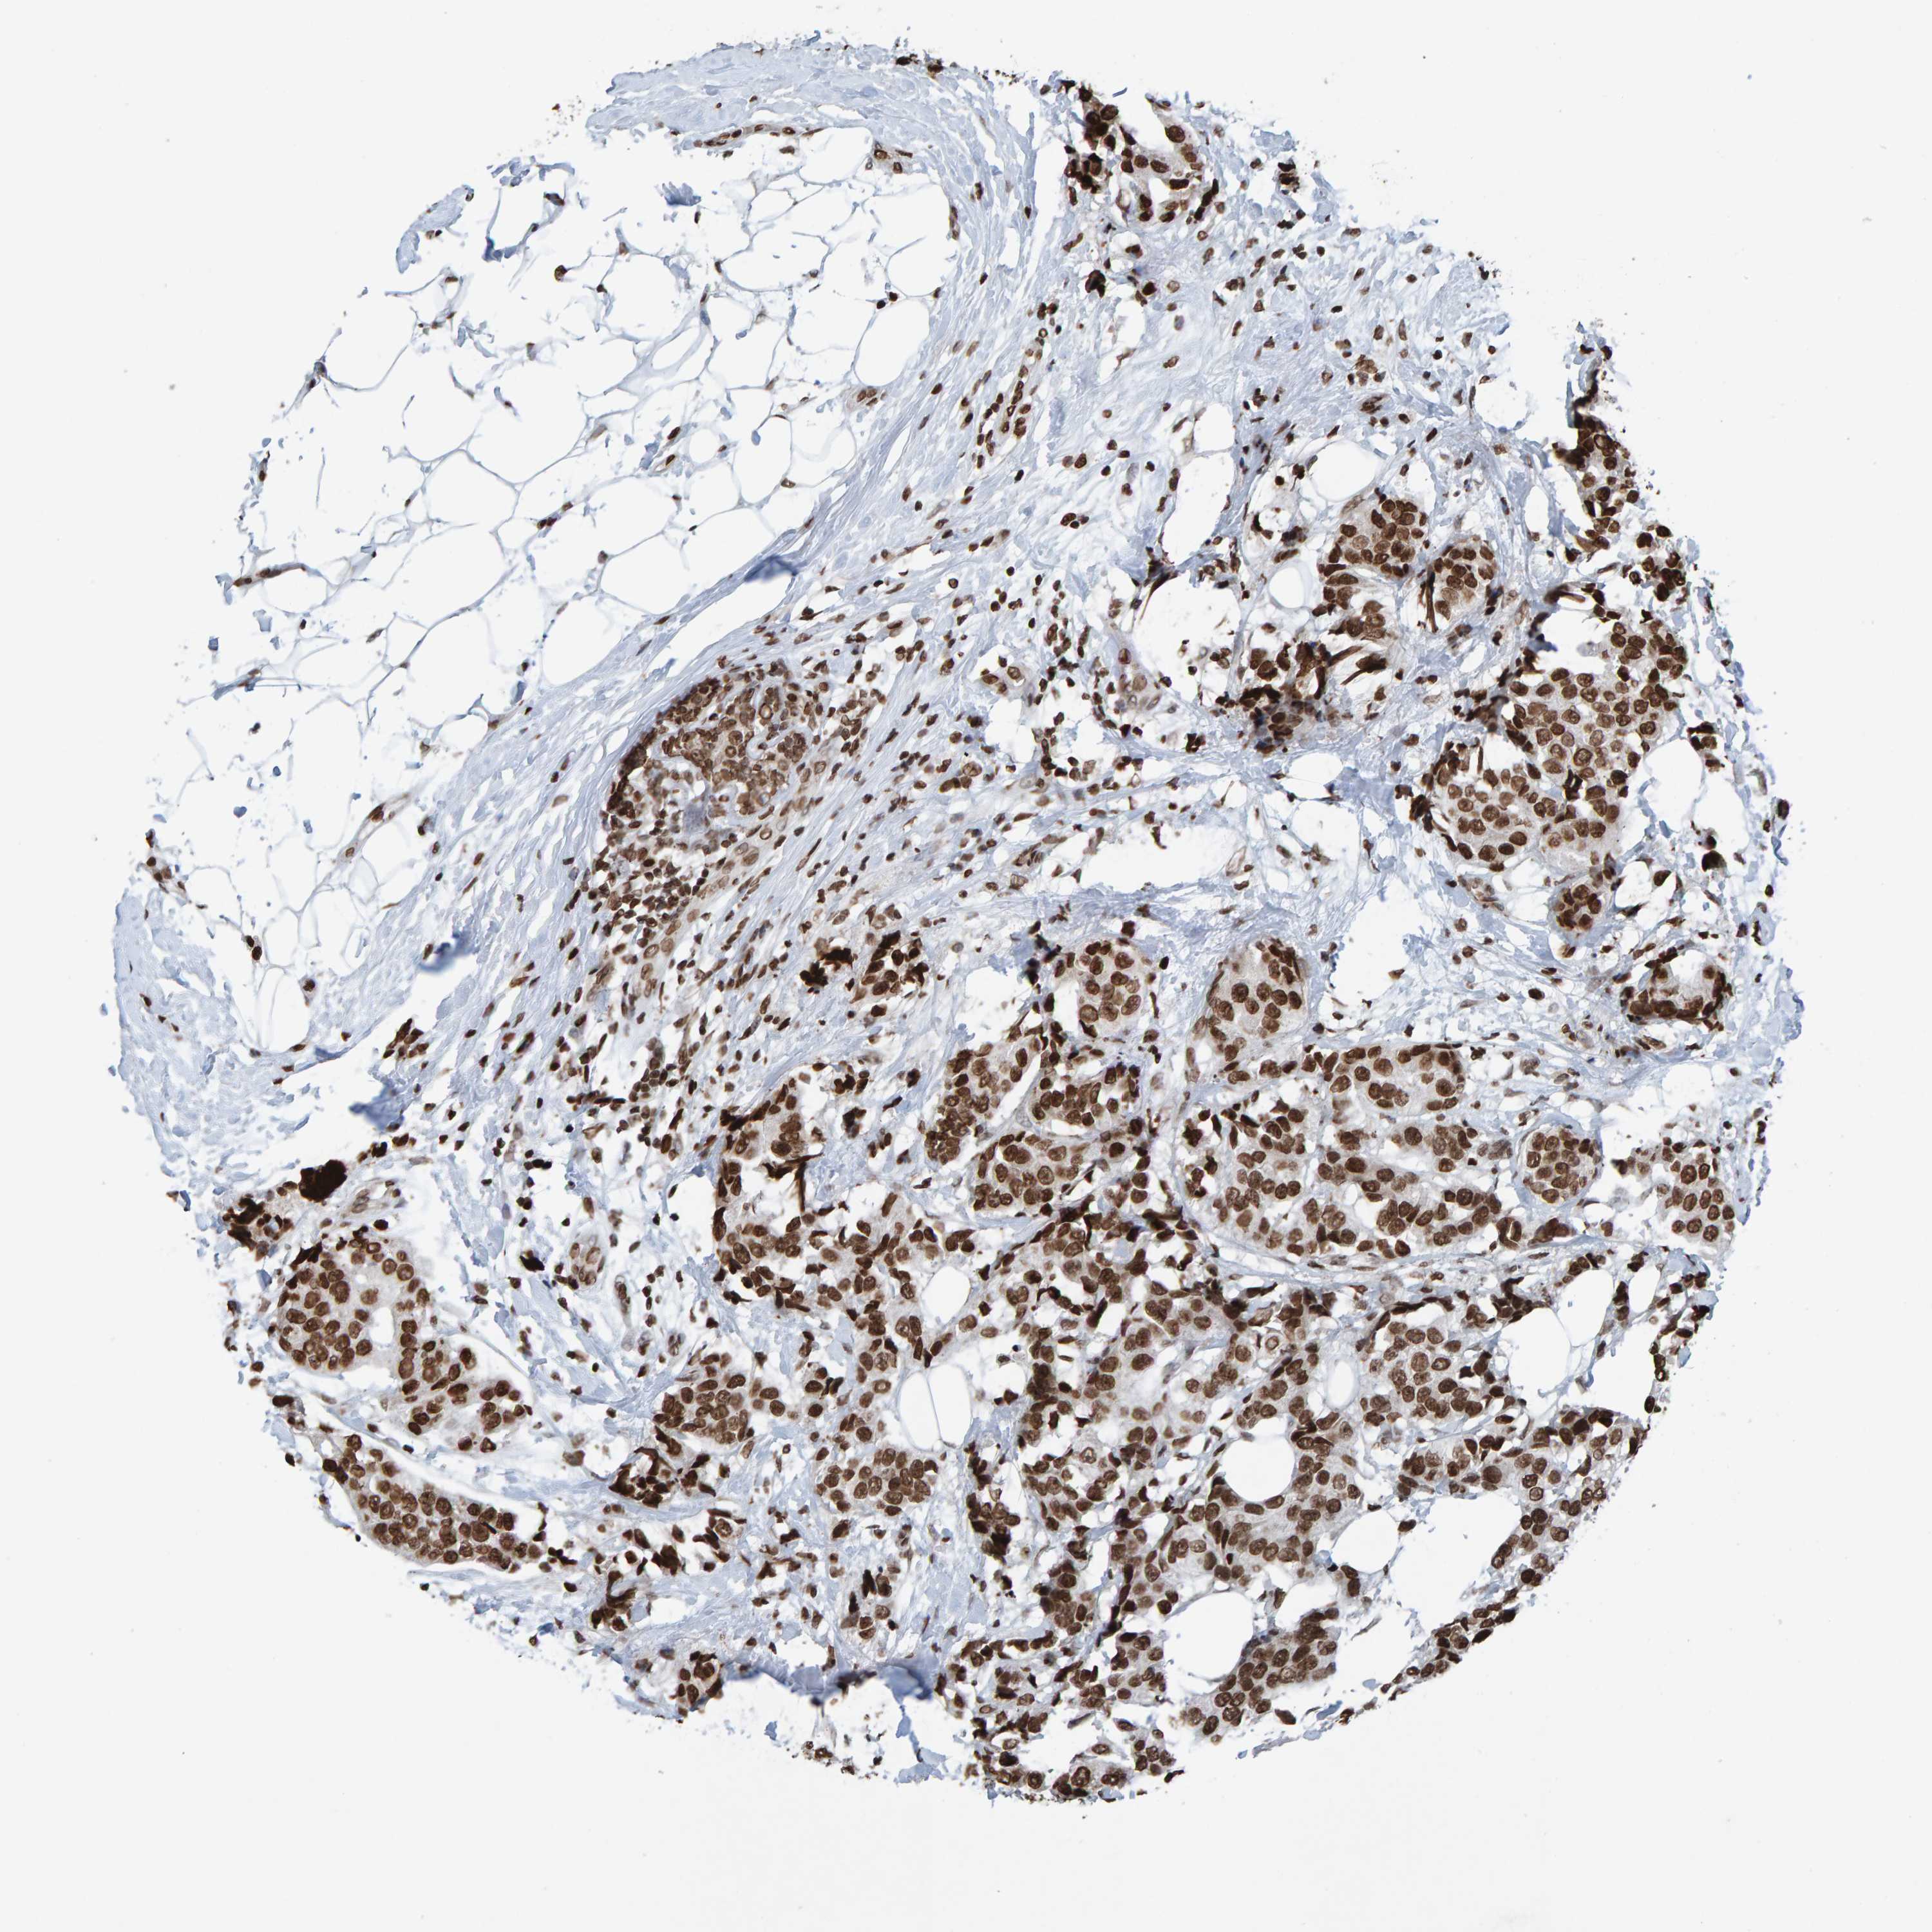

CANCER BREAST CANCER Show tissue menu

BRCA TCGA BRCA VALIDATION PROTEIN EXPRESSION